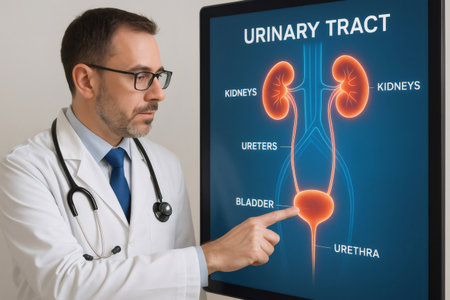

Doctor pointing at bladder on interactive display showing human urinary tract, kidneys, ureters, bladder and urethra